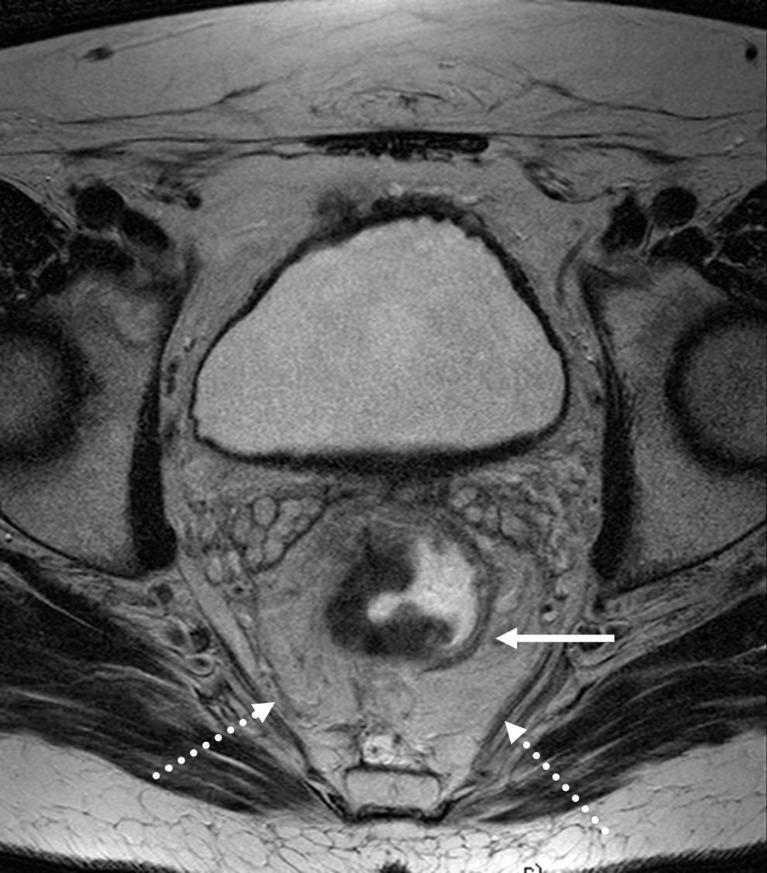

直肠癌的磁共振成像(MRI):全面综述

Magnetic resonance imaging (MRI) in rectal cancer: a comprehensive review.

Magnetic resonance imaging (MRI) has established itself as the primary method for local staging in patients with rectal cancer. This is due to several factors, most importantly because of the ability to assess the status of circumferential resection margin. There are several newer developments being introduced continuously, such as diffusion-weighted imaging and imaging with 3 T. Assessment of loco-regional lymph nodes has also been investigated extensively using different approaches, but more work needs to be done. Finally, evaluation of tumours during or after preoperative treatment is becoming an everyday reality. All these new aspects prompt a review of the most recent advances and opinions. In this review, a comprehensive overview of the current status of MRI in the loco-regional assessment and management of rectal cancer is presented. The findings on MRI and their accuracy are reviewed based on the most up-to-date evidence. Optimisation of MRI acquisition and relevant regional anatomy are also presented, based on published literature and our own experience.

磁共振成像(MRI)已成为直肠癌患者局部分期的主要方法。这归因于几个因素,最重要的是其能够评估环周切缘的状态。不断有一些新进展被引入,如扩散加权成像和3T成像。使用不同方法对局部区域淋巴结的评估也已得到广泛研究,但仍需开展更多工作。最后,术前治疗期间或之后对肿瘤的评估正成为日常现实。所有这些新情况促使我们对最新进展和观点进行综述。在本综述中,对MRI在直肠癌局部区域评估和管理中的当前状况进行了全面概述。基于最新证据对MRI的发现及其准确性进行了综述。还根据已发表的文献和我们自己的经验介绍了MRI采集的优化及相关区域解剖结构。